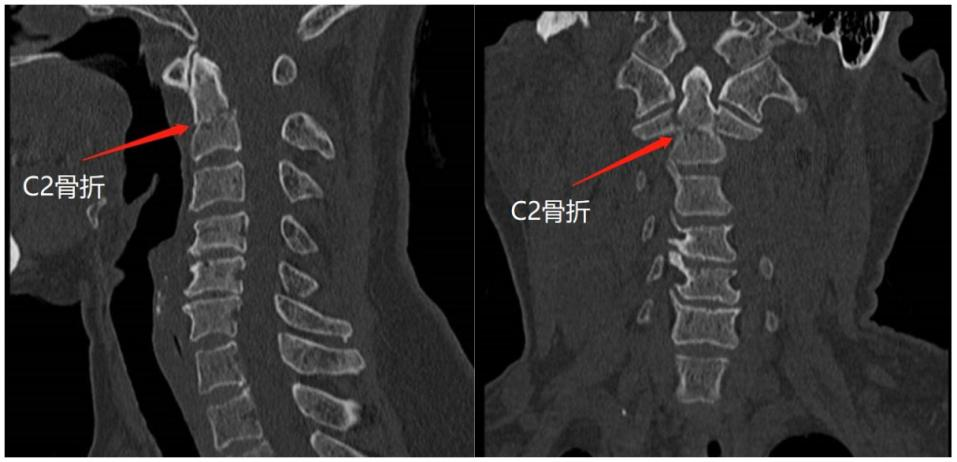

齿状突骨折

- 创伤性齿状突骨折(ct)图片尺寸1200x1600